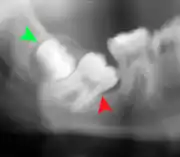

Coronectomy of impacted wisdom tooth post-op xray showing root remnants (red arrow) and inferior alveolar nerve (green arrow)

Coronectomy is a procedure where the crown of the impacted wisdom tooth is removed, but the roots are intentionally left in place. It is indicated when there is no disease of the dental pulp or infection around the crown of the tooth, and there is a high risk of inferior alveolar nerve injury.[31]

Coronectomy, while lessening the immediate risk to the inferior alveolar nerve function has its own complication rates and can result in repeated surgeries. Between 2.3% and 38.3% of roots loosen during the procedure and need to be removed and up to 4.9% of cases require reoperation due to persistent pain, root exposure or persistent infection. The roots have also been reported to migrate in 13.2% to 85.9% of cases.[31]